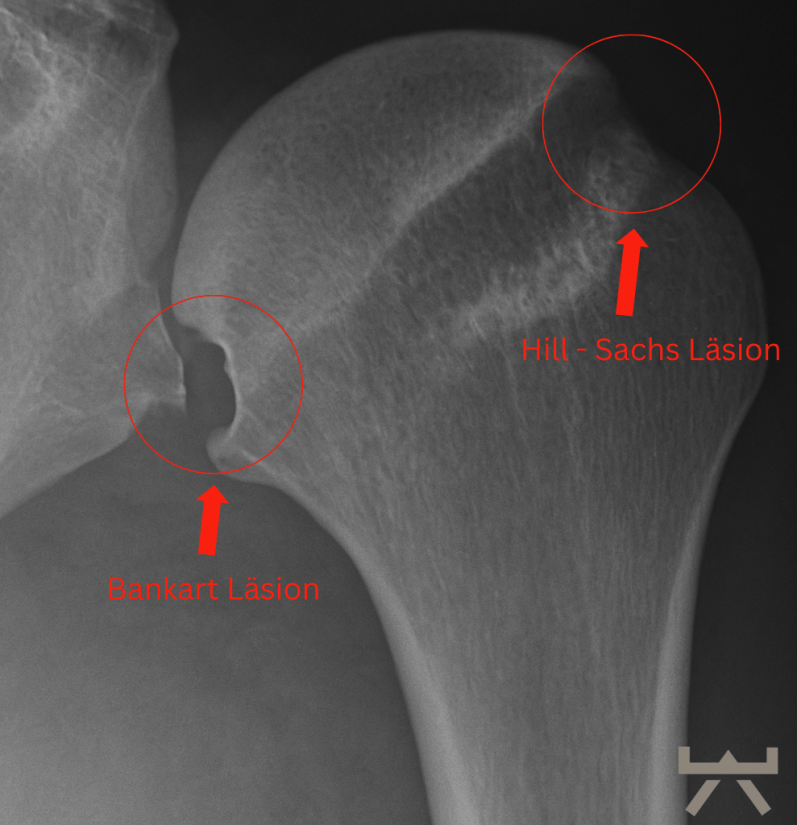

In einigen Fällen können bei einer traumatischen Schulterluxation mehrere Strukturen beschädigt werden. Zunächst kann einmal das Bindegewebe der Kapsel und/oder des Labrums gedehnt werden oder reißen. Zum anderen kann sich eine knöcherne „Bankart-Läsion“ entwickeln, bei der es durch den Aufprall zu einer Fraktur am unteren Ende der Schulterpfanne kommt. Dies geht häufig mit einer „Hill-Sachs-Läsion“ einher, einer Delle in der Schulterkopf selbst. Eine Röntgenaufnahme der Schulter kann dies entweder zeigen oder ausschließen.

Bei einer (traumatischen) Auskuglung ist es wichtig, dass eine Bildgebende Untersuchung durchgeführt wird, um weitere Läsionen und mögliche Brüche auszuschließen.